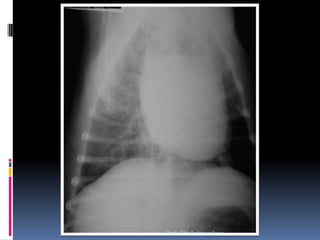

Exame radiográfico torácicoCuidados – padrões eventualmente detectados – diferenciação da sua relevânciaSilhueta cardíacaAumentos verdadeiros (posicionamento) x Gordura mediastinal – velhinhos obesosComo diferenciar (3 projeções)Gatos velhos – RX – “coração preguiçoso”Dificuldades na avaliação – escolha a Projeção VDProfa. Tilde Rodrigues Froes

Exame radiográfico torácicoCuidados – padrões eventualmente detectados – diferenciação da sua relevânciaASPECTOS RELEVANTESAumento do Átrio esquerdo (Endocardiose de mitral)Aumento generalizado (Miocardiopatia x efusão pericárdica x massa)Imagem de “D”Invertido – associado a quadros pulmonares e colapso de traquéiaProfa. Tilde Rodrigues Froes

Animal: NEGUER, canino, macho, 11 anosHx: Ascite, sinais de creptação e sopro na ausculta pulmonar - asciteProfa. Tilde Rodrigues Froes

Profa. Tilde Rodrigues Froes